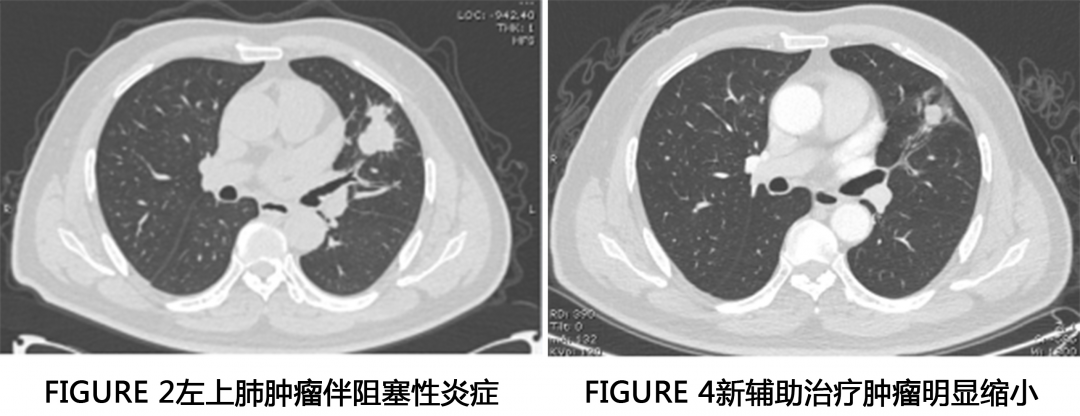

患者陈先生68岁。2月前因右侧肋部外伤到当地医院就诊,拍了胸部CT显示左舌段占位伴阻塞性改变,纵隔及左侧腋窝淋巴结肿大,肺癌可能性大。

患者在多方医生的帮助下,为进一步缩小肿瘤、降期及增加手术机会,做了新辅助化疗与靶向治疗。化疗方案为:培美曲塞二钠1.0 D1+卡铂 0.6 D1;基因检测:EGFR21外显子突变、Hert2突变,2021-01-11加用阿美替尼治疗。

患者在多方了解下,近期来我科室找到了邵丰主任,复查了CT。

邵主任在多方判断下,病人可以手术切除病灶,术前分期检查也未见明显远处转移。手术方式为全麻单孔胸腔镜下行左上肺叶切除+淋巴结清扫术。

患者进行新辅助化疗后手术难度明显增大,尤其是病灶退缩部位,硬的像钢板,毫无间隙和层次可言,需要医生的耐心和胆量。邵主任从医多年,手术很顺利,历时1.5小时,术中出血仅50ml。

术中见主肺动脉窗淋巴结及肺门淋巴结冻结明显,肺门结构纤维化明显,分离困难,完美避开喉返神经,术后患者也无明显声音嘶哑症状。